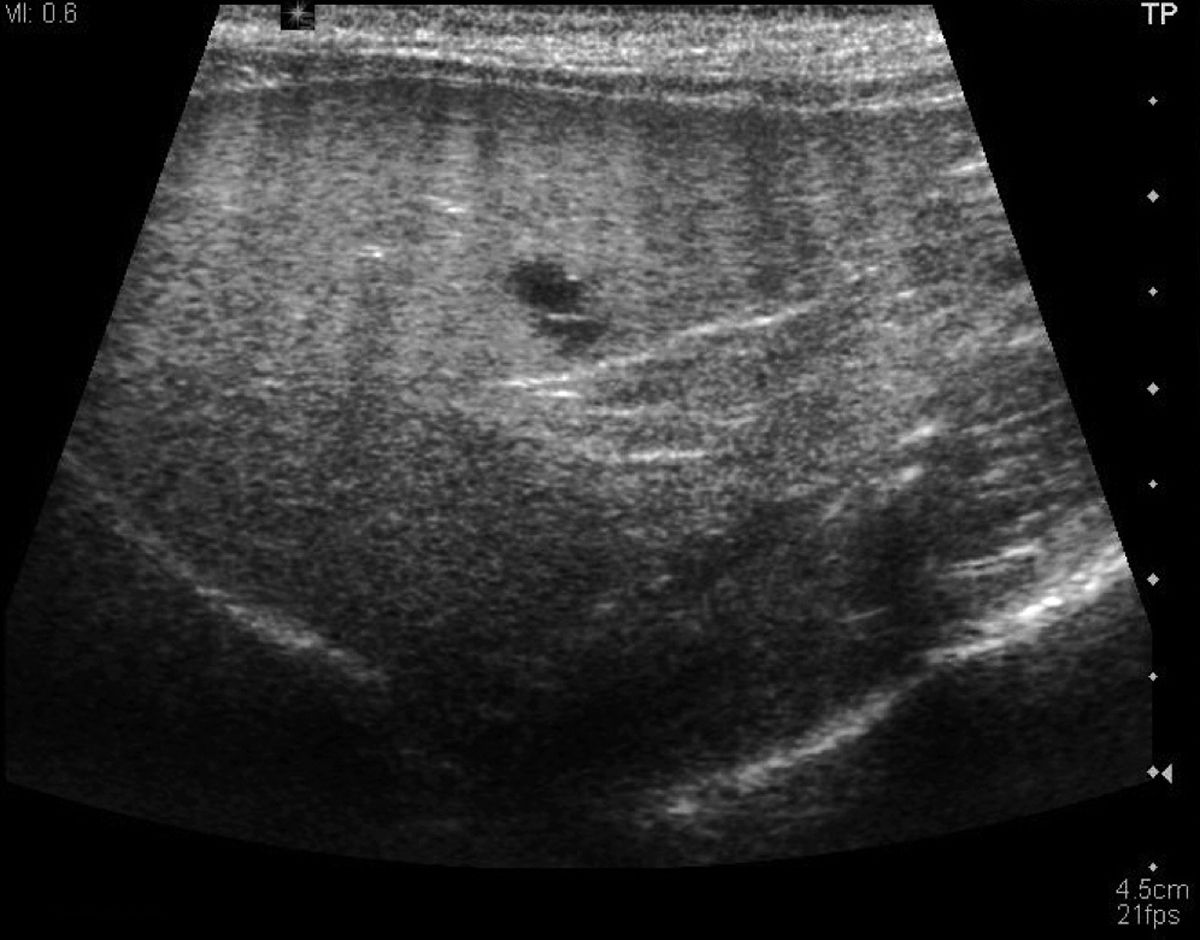

Die dunklen Flecken entsprechen Lebermetastasen. Braune Flecken auf der Haut. Hallo zusammen eine Freundin hat mir grade ein Bild von ihrem Oberarm geschickt auf dem sie seit 2 Tagen einen kleinen Fleck hat der auch so etwas wie auf der Haut liegt.

September eine PET-Untersuchung machen. Helle Flecken auf der Leber bei Ultraschall Helle Flecken bedeuten im Ultraschall hyperreflexiv. Es entsteht aus dem roten Farbstoff der Blutzellen und wird normalerweise mit Hilfe der Leber ausgeschieden.